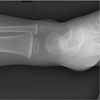

The skull, the long bones of the extremities, and the clavicle are most susceptible to injury following a seemingly insignificant accidental fall.5,6 However, these are the same bones, along with the ribs, that are fractured when a child is intentionally injured. Although serious sequelae, such as depressed skull fractures, can result from a low fall, the vast majority of children do not sustain major injury.5-8

The clinician has to also consider the possibility of non-accidental trauma in any child with any type of fracture--especially in infants younger than 1 year. Banaszkiewicz and associates19 found that abuse was underestimated in 28.4% of patients younger than 1 year who were brought to the clinician with a fracture. In addition, occult fractures are also most likely to be discovered on a skeletal survey in children of this age.21 Although leg bone fractures can occur accidentally if a child runs and falls with a twisting motion while the foot remains stationary on the floor, such fractures suggest abuse in the non-ambulatory patient.

As with skull fractures, rib fractures are of extreme concern. The distal or mid clavicle can be easily injured in an accidental fall, but a fracture of the most medial aspect of the clavicle is particularly worrisome.22 The long bones are commonly injured in an accident, but in a child older than 1 year, the long bones (femur, humerus, tibia, and forearm bones) are also the most common location of non-accidental injury.22

Imaging studies are often necessary in the assessment of an infant or young child with an obvious or suspected injury. The skeletal survey (Table 3) is recommended and is mandatory in all cases of suspected abuse in children younger than 2 years.24 However, it has little value in children older than 5 years.25 Patients between ages 2 and 5 years are assessed on an individual basis.

If clinical findings point to a specific injury site, that anatomic region should be evaluated with a radiograph--regardless of the child's age.25 An experienced radiologist should be present while imaging is performed to ensure that high-resolution images of good quality are obtained. If the initial skeletal survey is unremarkable but abuse is still strongly suspected, a repeated skeletal survey in 2 weeks may offer greater yield in discovering occult fractures.26 A bone scan is another option for searching for occult fractures: the need for this modality is determined on a case-by-case basis.